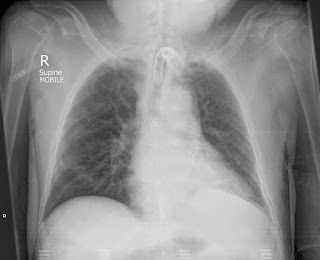

الشوائب الشائعة (جميع أشكال التصوير الشعاعي)

الأجسام المانعة لمرور الاشعة على جسم المريض (مثل المجوهرات (مثل القلائد والحلق) والملابس (مثل الأزرار) والشعر (مثل ذيل الحصان وضفائر الشعر وما إلى ذلك)